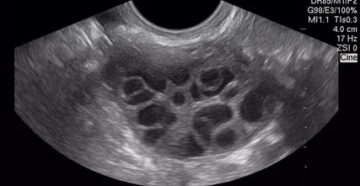

Мультифолликулярные яичники Основным механизмом нарушения фертильности при мультифолликулярных (или поликистозных) яичниках является хроническая ановуляция. Международная…